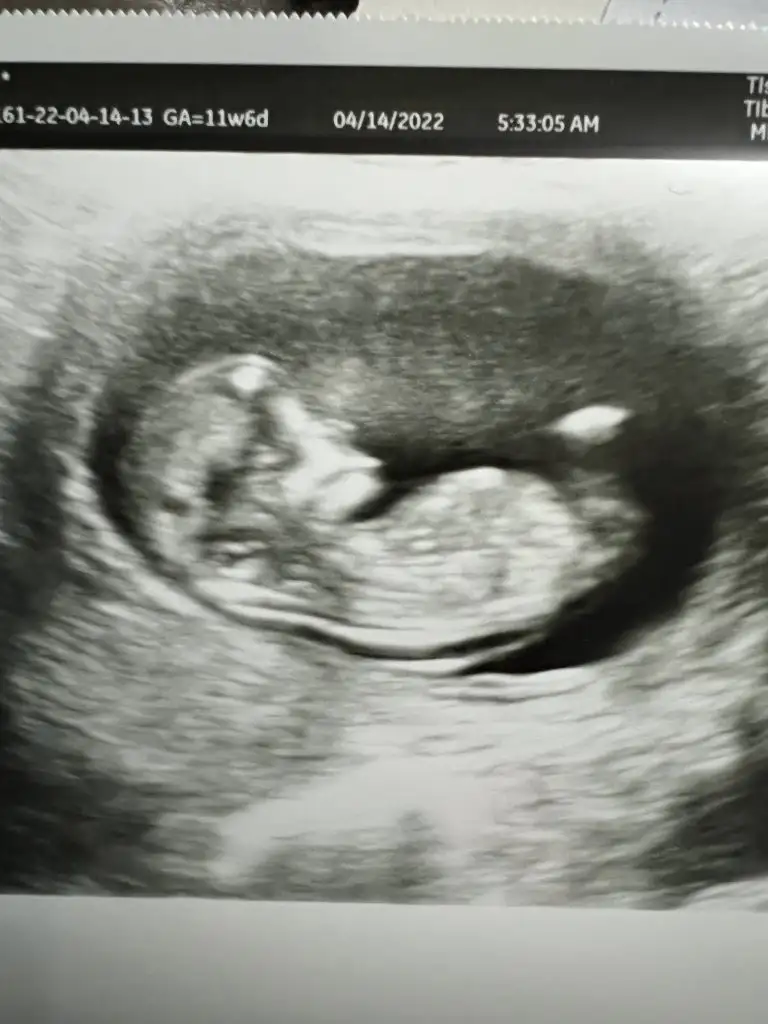

ilk foto kız ikinci foto hala erkek gibi. Baksana kuzuum ilkinde bebeğin uzandığı yer paralel düz gibi , ikincisinde yukarı kayan bir şekli var. Keşke doktorlar gibi bizde hareketli anlarına baksak. Doktlar bence 13 haftalarda cinsiyet söyleyebilir ama korkuyorlarSelamlarrr yine benBu kez 11+6 usg görüntüsüyle geldim tekrar bakarsanız çok sevinirim